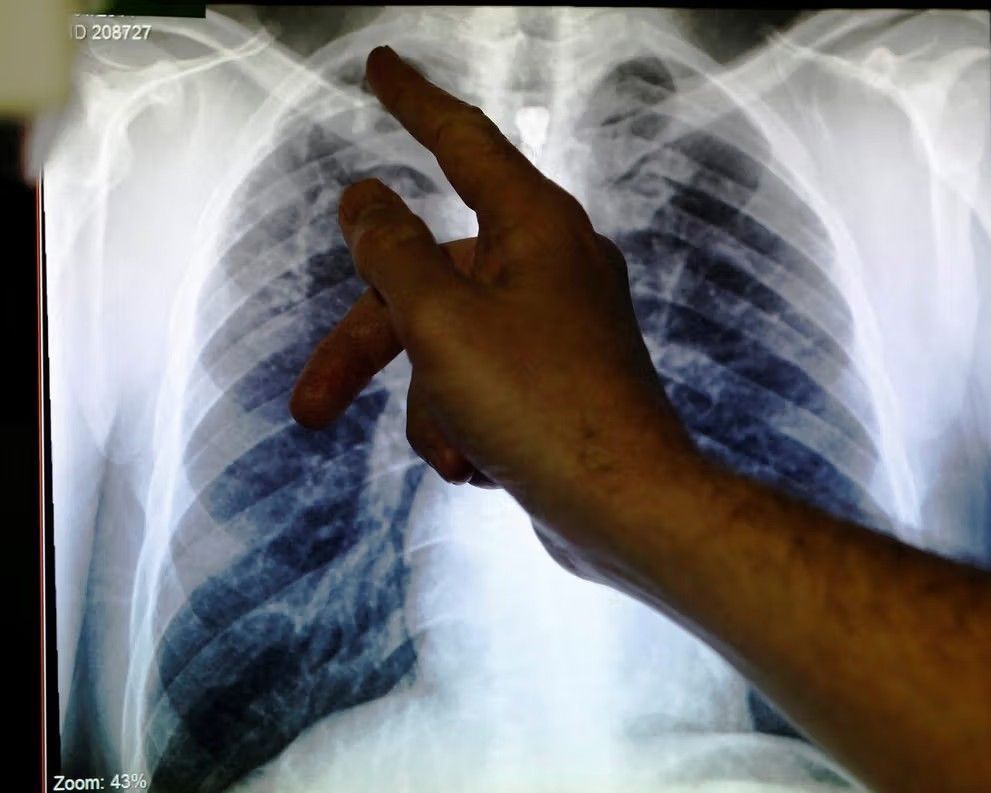

سازمان بهداشت جهانی می‌گوید توبرکلوز همچنان یک تهدید جدی در افغانستان است

سازمان بهداشت جهانی به‌مناسبت روز جهانی توبرکلوز اعلام کرده است که سالانه هزاران نفر در افغانستان به این بیماری مبتلا می‌شوند. ادوین سینیزا سلوادور، رئیس این سازمان در افغانستان، هشدار داد توبرکلوز همچنان یک تهدید جدی بهداشتی در این کشور است.

این نهاد وابسته به سازمان ملل روز سه‌شنبه، چهارم حمل، همزمان با روز جهانی توبرکلوز در یادداشتی در شبکه اجتماعی اکس نوشت که بسیاری از موارد این بیماری در افغانستان بدون تشخصی باقی می‌مانند.

این سازمان همچنین با تاکید بر گسترش تشخیص زودهنگام، بهبود دسترسی به تداوی و نادیده گرفته نشدن بیماران خواستار اقدام جمعی برای پایان دادن به توبرکلوز شده است.

رئیس سازمان جهانی بهداشت در افغانستان گفت: «پایان دادن به توبرکلوز تنها یک آرزو نیست، بلکه هدفی قابل دستیابی است.»

بر اساس داده‌های سازمان جهانی بهداشت، بیماری سل یکی از ده عامل مهم مرگ‌ومیر در جهان است و نزدیک به ده میلیون نفر سالانه به این بیماری مبتلا می‌شوند.

براساس آمار سازمان جهانی بهداشت در سال ٢٠٢٣ میلادی حدود ٨٠ هزار مورد ابتلا به سل توبرکلوز در افغانستان ثبت شده است.